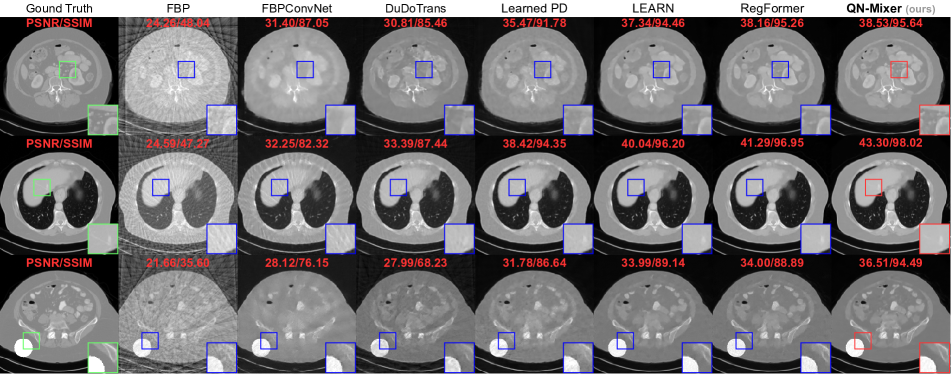

Figure 4: Visual comparison on AAPM. From top to bottom: the results under the following conditions: first (nv=32,N1)subscript𝑛𝑣32subscript𝑁1(n_{v}=32,N_{1}), second (nv=64,N1)subscript𝑛𝑣64subscript𝑁1(n_{v}=64,N_{1}), third (nv=32,N0)subscript𝑛𝑣32subscript𝑁0(n_{v}=32,N_{0}). The last row presents out-of-distribution (OOD) results with a randomly overlaid circle on a test image. The display window is set to [1000,800]1000800\left[-1000,800\right] HU.

Quantitative comparison.  We compared our model with state-of-the-art baselines on two public datasets. For AAPM, models were trained and tested across three projection views (nv{32,64,128}subscript𝑛𝑣3264128n_{v}\in\{32,64,128\}) and three noise levels, namely no noise N0=0subscript𝑁00N_{0}=0, low noise N1=106subscript𝑁1superscript106N_{1}=10^{6}, and high noise N2=5×105subscript𝑁25superscript105N_{2}=5\times 10^{5} (see Tab. 1). For DeepLesion, models were trained and tested on the same three projection views and a noise level of N1=106subscript𝑁1superscript106N_{1}=10^{6} (see Tab. 2). Visual results are provided in Fig. 4 (AAPM) and Fig. 5 (DeepLesion). Impressively, our method achieves state-of-the-art results on DeepLesion across all projection views. It outperforms the second-best baseline, RegFormer, with an average improvements of +2.232.23+2.23 dB in PSNR and +1.021.02+1.02% in SSIM. On AAPM without noise, we achieve state-of-the-art results across all projection views and improve the second best by an average +1.651.65+1.65 dB and +0.58%percent0.58+0.58\%. In the presence of low noise, QN-Mixer achieves state-of-the-art results performance in all cases except nv=128subscript𝑛𝑣128n_{v}=128 with 0.110.11-0.11 dB and shows an average improvements of +0.330.33+0.33 dB and +0.350.35+0.35% over RegFormer. With high noise, our method performs nearly on par in nv=32subscript𝑛𝑣32n_{v}=32 (0.020.02-0.02 dB and 0.290.29-0.29%), achieves state-of-the-art in nv=64subscript𝑛𝑣64n_{v}=64 (+0.20.2+0.2 dB and +0.080.08+0.08%), and competes closely in nv=128subscript𝑛𝑣128n_{v}=128 (0.010.01-0.01 dB and +0.080.08+0.08%). As noise increases, we attribute the decline in improvement to the compressed gradient information in the latent BFGS, influenced by sinogram changes, and the utilization of the FBP algorithm instead of the pseudo-inverse.

In medical imaging, where training data predominantly consists of normal patient images, it is imperative to develop methods that generalize to scans with lesions or anomalies. To address this challenge, we conducted an experiment to evaluate model performance on out-of-distribution (OOD) textures. The frozen models were tested with CT images featuring a randomly positioned white circle with no noise added to the sinograms, as illustrated in the third row of Fig. 4. In Tab. 3, QN-Mixer attains state-of-the-art results across all nvsubscript𝑛𝑣n_{v} views. First-order unrolling networks such as LEARN and RegFormer exhibit significant PSNR degradation of 3.13.1-3.1 dB and 4.224.22-4.22 dB, respectively, for nv=32subscript𝑛𝑣32n_{v}=32, while our method demonstrates a milder degradation of 2.672.67-2.67 dB.

Visual comparison.  As it can be seen on Fig. 4 and Fig. 5, FBPConvNet and DuDoTrans exhibit noticeable blurry images with severe artifacts when nv=32subscript𝑛𝑣32n_{v}=32. While Learned PD and LEARN show satisfactory performance, they struggle with intricate details, like in the liver and spine. In contrast, RegFormer produces high-quality images but faces challenges in generalizing to OOD data. QN-Mixer excels in producing high-quality images with fine details, even under challenging conditions such as nv=32subscript𝑛𝑣32n_{v}=32 views and OOD data.